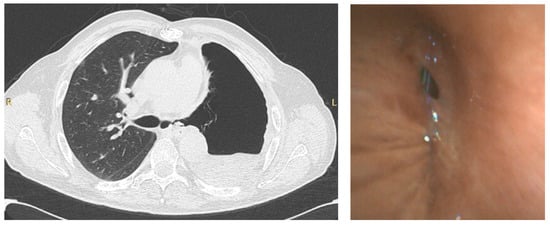

Urgent indications include lung cancer diagnosis (lung mass or mediastinal/hilar lymphadenopathy), foreign body aspiration, and suspected pulmonary infection in immunocompromised patients (Table 1). In the latter case, early bronchoscopy is essential because it may rule out the presence of a co-infection, thus allowing timely treatment. Moreover, in patients that underwent lung transplantation, transbronchial biopsies have an important role in identifying the presence of acute cellular rejection. Figure 2 shows the CT scan of a transplanted patient who was infected by SARS-CoV-2 during the recovery after lung transplant. The persistence of consolidations in the right lower lobe despite treatment for COVID-19 suggested a possible acute cellular rejection. However, the patient was histologically diagnosed with SARS-CoV-2 pneumonia.

Chest X-ray (CXR) (left), CT scan (right) of a lung transplanted patient who was infected by SARS-CoV-2 during the recovery after transplant. The patient underwent a tranbronchial bronchial biopsy and was histologically diagnosed with SARS-CoV-2 pneumonia.